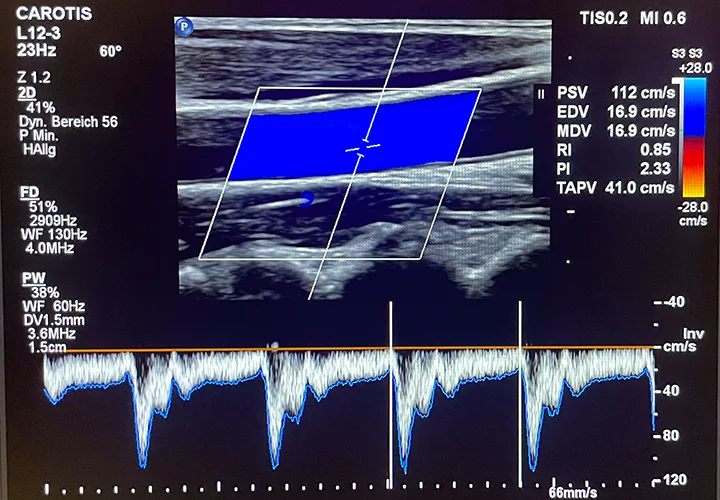

Gefäßdiagnostik

Karotis-Doppleruntersuchung

Früherkennung von Verengungen oder Verkalkungen der Halsschlagadern zur Einschätzung des Schlaganfallrisikos.